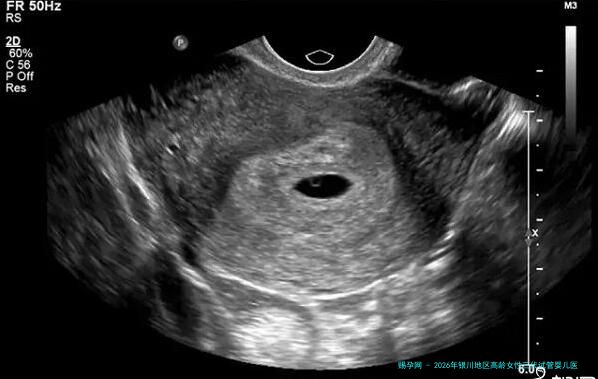

我们需要精确1个概念:因何高龄女性更加需要注意三代试管技术?跟着年龄增多,女性卵子质量下降,染色体异常的风险明显增高,这直接导致自然受精率减少、流产率升高。而第三代试管婴儿技术(PGT) 的核心优点体现在,能在胚胎移植前行行基因学筛查,挑选出染色体正常的优质胚胎进行移植,进而有效提高着床,并显著减少因染色体问题导致的胎停和流产风险。至于有反复流产史、或已然知晓存留染色体异样的高龄夫妇,这个技术提供了更加准确的生育解决方案。